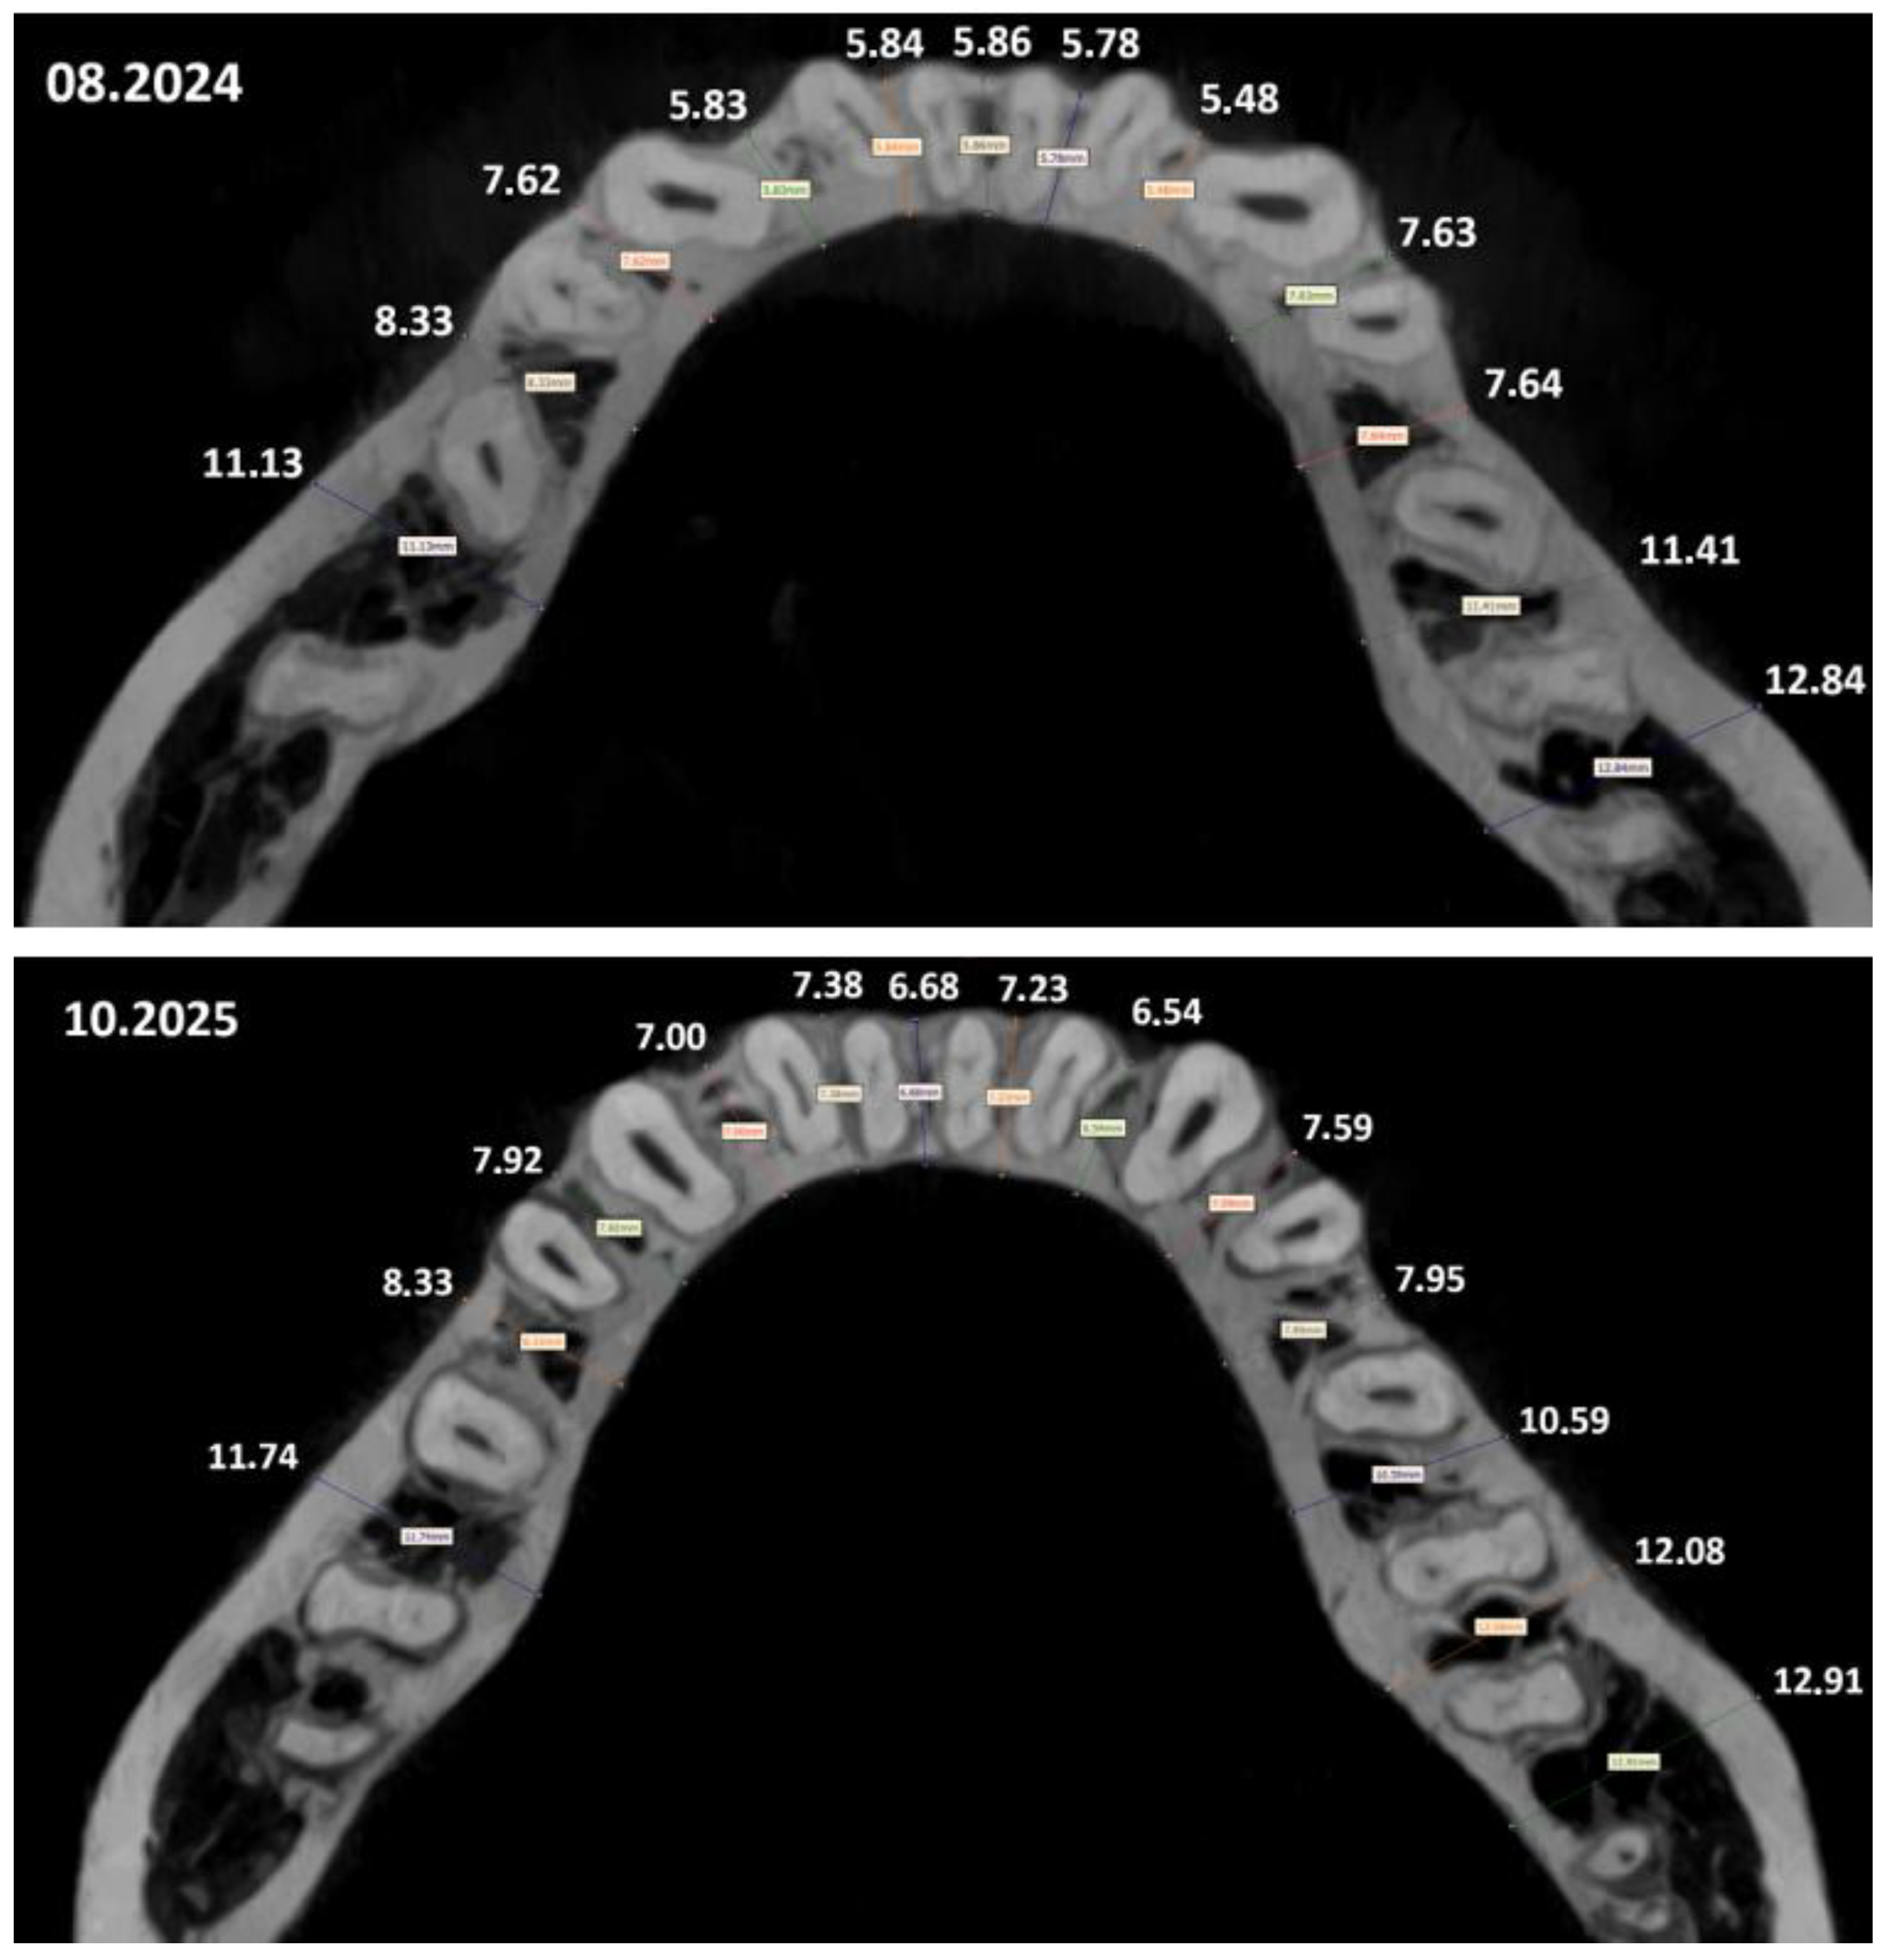

| Mandibulae | |||

| Segment | August 2024 (mm) | October 2025 (mm) | Change (mm) |

| 1 | 11.13 | 11.74 | +0.61 |

| 2 | 8.33 | 8.33 | 0.00 |

| 3 | 7.62 | 7.92 | +0.30 |

| 4 | 5.83 | 7.00 | +1.17 |

| 5 | 5.84 | 7.38 | +1.54 |

| 6 | 5.86 | 6.68 | +0.82 |

| 7 | 5.78 | 7.23 | +1.45 |

| 8 | 5.48 | 6.54 | +1.06 |

| 9 | 7.63 | 7.59 | −0.04 |

| 10 | 7.64 | 7.95 | +0.31 |

| 11 | 11.41 | 10.59 | −0.82 |

| 12 | 12.84 | 12.08 | −0.76 |